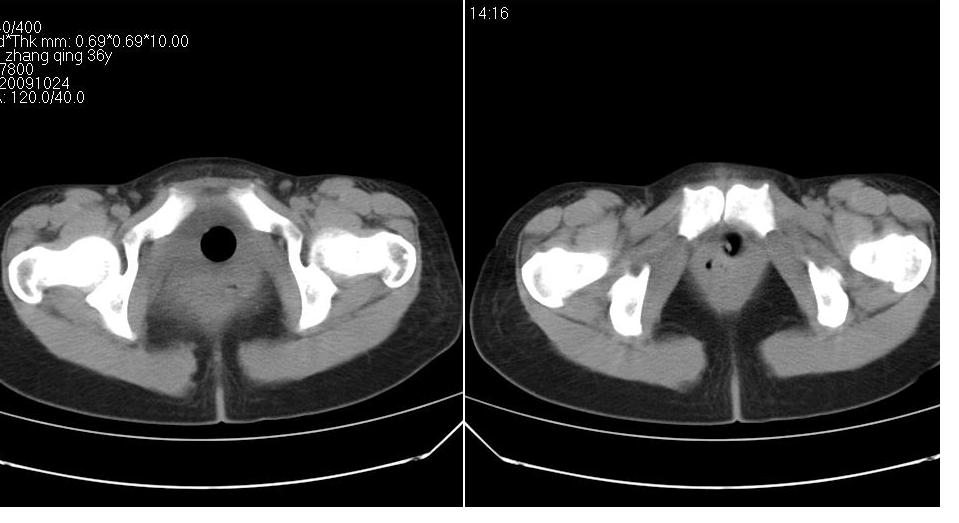

标题: CT22811:女 36岁,B超提示右侧附件囊性占位。 [打印本页]

标题: CT22811:女 36岁,B超提示右侧附件囊性占位。

右侧卵巢囊肿

右侧卵巢囊肿。

手术结果证实为右侧输卵管囊肿。

输卵管囊肿罕见,从影像上无法同卵巢囊肿区分。

输卵管囊肿一般是指输卵管受病原体感染以后,由于白细胞的浸润形成内膜肿胀、间质水肿、渗出,输卵管粘膜上皮脱落,如果输卵管急性期炎症没得到及时有效的治疗就形成了输卵管积脓。输卵管积脓在炎症消退后,脓液逐渐被吸收,腔内积液由脓性变为浆液性,则成为输卵管囊肿。

还是报右侧附件区良性囊性占位性改变       至于输尿管或卵巢囊肿不太好鉴别